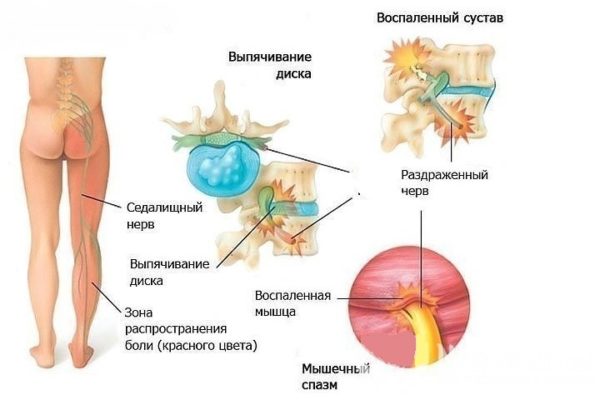

Важно! Каждый пятый человек в мире страдает от болезней седалищного нерва и поясничной боли. У каждого шестого поясничный болевой синдром клинически подтвержден.

Защемление седалищного нерва

Механическое смещение одного из поясничных позвонков, переохлаждение, локальная инфекция, опухоли, деградация тканей, могут привести к воспалительному процессу в позвоночно-двигательном сегменте, последующим мучительным болям, вынужденным положениям тела. Очень распространённой причиной патологии в поясничном отделе позвоночника является неверное распределение нагрузки на поясничный отдел позвоночника, когда дополнительный вес (а иногда и собственный вес) поднимаются с единственным рычагом в поясничном отделе позвоночника. Частым заболеванием в поясничном отделе позвоночника являются грыжи межпозвоночных дисков — выпячивания пульпозного ядра диска за пределы его фиброзного кольца. В 48 % случаев межпозвоночные грыжи локализуются на уровне L5-S1 пояснично-крестцового отдела, в 46 % случаев — на уровне L4-L5, и лишь в оставшихся 6 % случаев — между другими позвонками поясничного, шейного или грудного отделов позвоночника.

Зачастую это болезненная область, особенно между позвонком L5 и крестцом и между L4 и L5, которые несут наибольшую нагрузку. Болезненные ощущения в этой зоне могут происходить либо от межпозвоночных дисков (ущемление или грыжа диска), либо от нервов, которые проходят на этом уровне (седалищный нерв), либо от связок и/или мышц, которые поддерживают всю структуру позвонков.